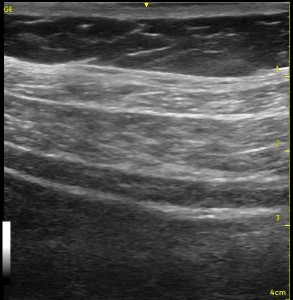

Sometimes, you can’t get the needle right where you want it, or a few confirmatory injections of local anesthetic distorts the local ‘architecture’ of the tissue. If you have done lots of TAP blocks, this has happened to you without question! You start with an awesome image, and end up with something like the image below.

Look at the images below. They appear to be a series of pictures arranged from the beginning of an injection to the end. In fact, no further injection is added. The first image is taken at the periphery of a TAP block, and the subsequent images are taken as the probe is slid closer to the center of the injection. They confirm that the needle is adequately placed within the appropriate plane though the central position is a bit difficult to interpret.